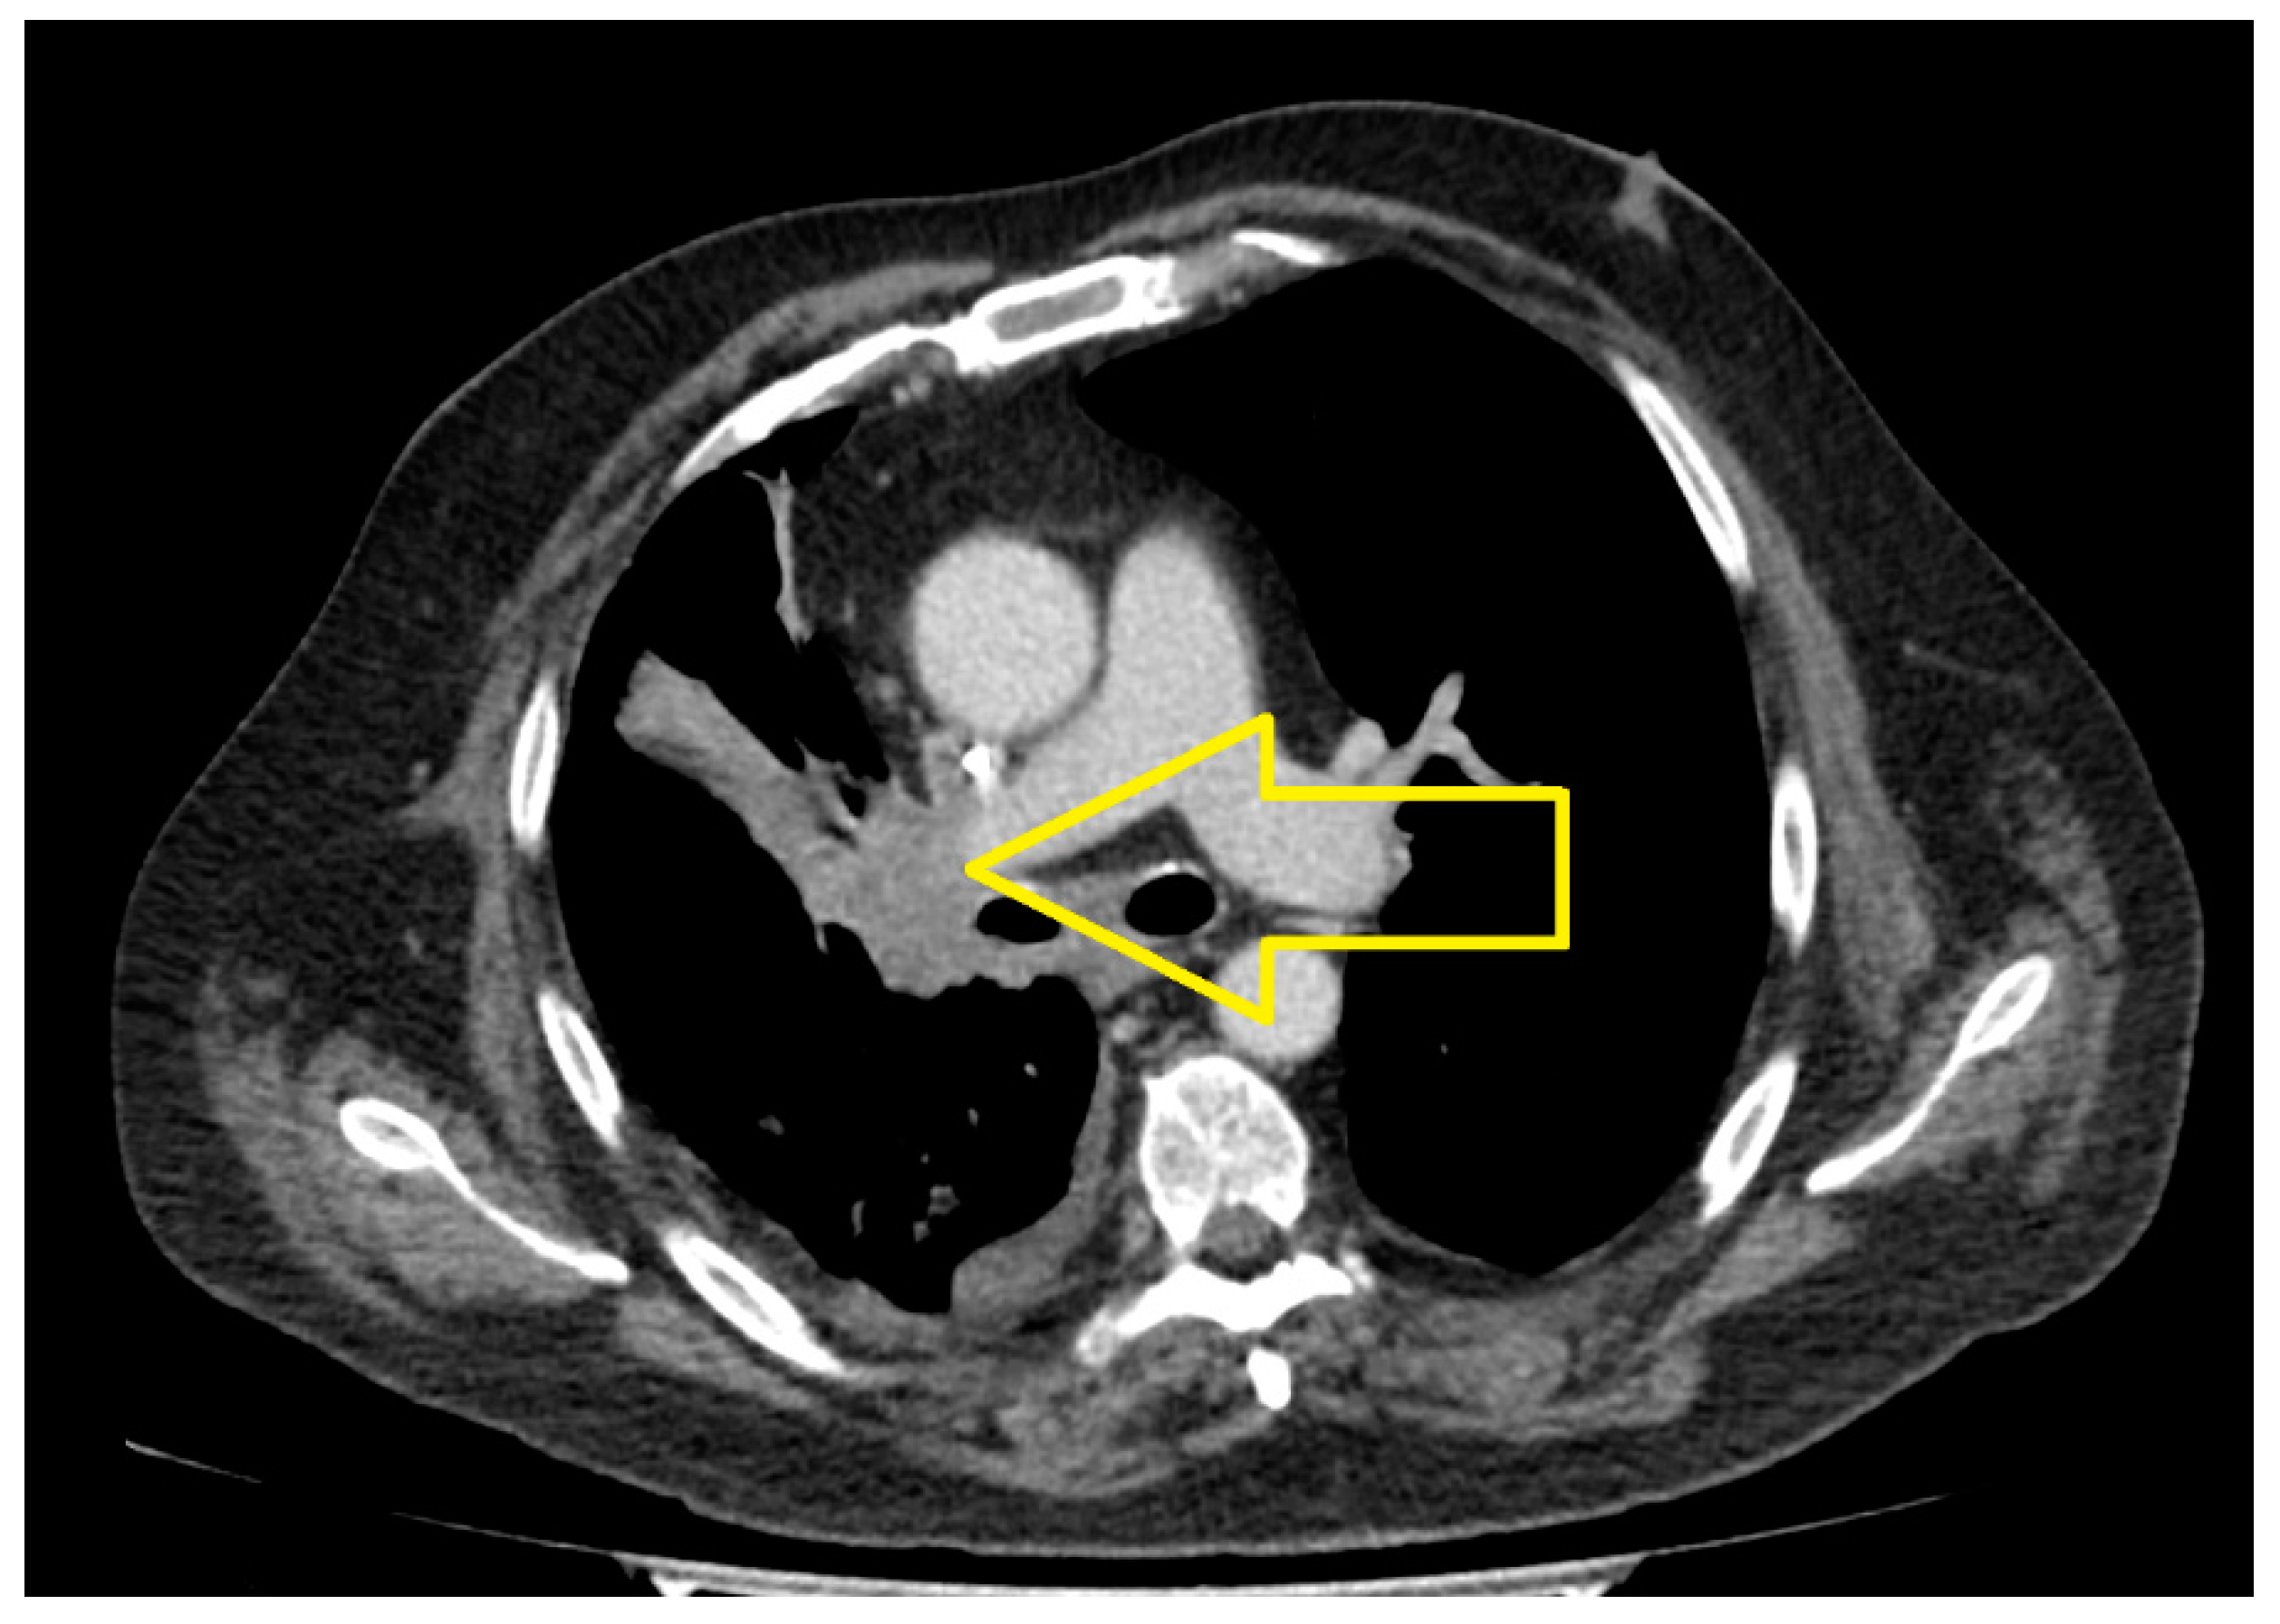

2. Case Presentation